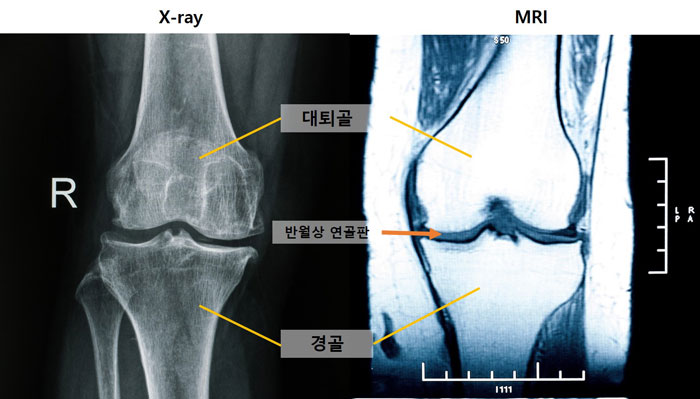

[사진 왼쪽부터] 엑스레이 및 MRI 무릎 사진

무릎 관절염을 조기에 발견할 수 있는 새로운 진단 지표가 확인됐다. 엑스레이에서 정상으로 진단된 무릎이라도, MRI에서 ‘중앙 대퇴골 연골 손상’ 소견이 관찰된다면 무릎 관절염이 이미 진행되고 있을 가능성이 높다는 사실을 국내 연구팀이 규명했다. 또한 MRI로 ‘내측 반월상 연골 돌출’이 관찰되면 관절염이 심각해질 위험이 높은 것으로 나타났다.

무릎 관절염 초기에는 연부조직(연골, 반월상 연골판 등)에서 먼저 변화가 발생하지만, 일반적으로 진단에 활용되는 엑스레이로는 이런 변화를 일찍 파악하는 데 한계가 있다. 연부조직을 관찰하기 용이한 MRI는 접근성이 떨어지며, 이처럼 서로 다른 특성을 가진 두 검사 방법의 연관성을 장기적으로 분석한 연구는 드물었다.

그 결과, 관절염 진행 시 가장 먼저 나타나는 변화는 ‘중앙 대퇴골 연골 손상’이었다. 이 손상은 엑스레이에서 정상으로 여겨지는 관절염 0기부터 관찰되어, MRI가 무릎 관절염 초기 변화를 확인하는 데 중요한 도구임을 보여줬다.